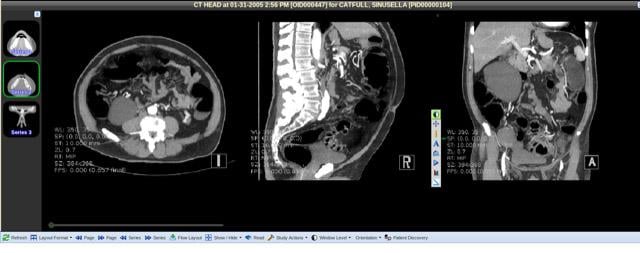

The 3-D tools include viewing a 3-D rendering that can be rotated; MIPS and MPRs, magnification, cross reference and locate tools, measurement tools and snapshot tools so an image can be saved as DICOM to the server for others to view. WebWorks provides browser-based viewing to any DICOM-capable picture archive and communication system (PACS) and vendor neutral archive (VNA), supports federating timelines across multiple DICOM servers and can be made available via URLs from within electronic medical records (EMRs). WebWorks 3D is available for locally installed systems or it can also be purchased as a service offering. The system is sized by the number of concurrent images that will be rendered.